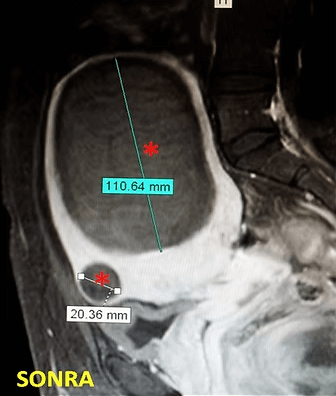

41 yaşında, kabızlık, gaz ve sık idrara çıkma şikayetleri var. Emar’da karını dolduran dev miyom (*) mevcut. Miyomektomi önerilmiş, ancak operasyonda rahimin alınabileceği söylenmiş. Embolizasyondan sonra dev miyomun ve bir başka küçük miyomun öldüğü ve küçüldüğü izleniyor. 7 ay sonra hasta şikayeti kalmamıştır.